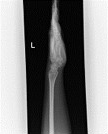

| 膝 | 手関節 | 足関節 |